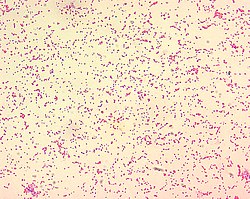

Brucella spp. are gram-negative in their staining morphology. Brucella spp. are poorly staining, small gram-negative coccobacilli (0.5-0.7 x 0.6-1.5 μm), and are seen mostly as single cells

B. ceti is a gram negative, non motile, aerobic bacteria. The cells are cocci, coccobacilli (short rods) with a diameter of 0.5–0.7 μm and a length of 0.6–1.5 μm. The arrangement of the cells are usually singular with occasional configurations in pairs or short chains. Cell growth occurs between 20 and 40 degrees celsius with the optimum temperature of 37 degrees celsius and is improved by the presence of blood or serum, supplemental CO2 is not required for cell growth. The ideal pH range is between 6.6 and 6.7.[3]